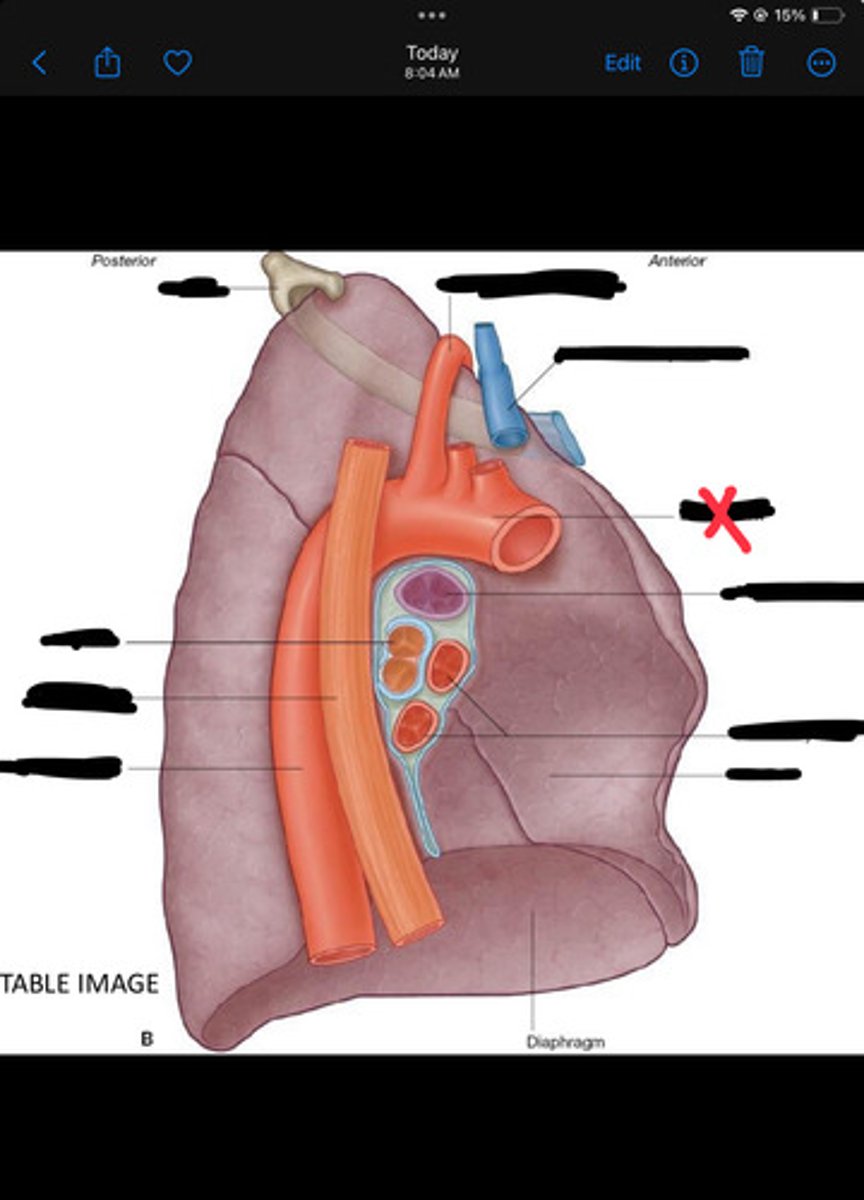

Diaphragm

Inferior vena cava

Superior vena cava

Subclavian vein

Right bracheocephalic vein

Subclavian artery

Esophagus

Bronchus

Rib 1

Left subclavian artery

Left brachiocephalic vein

Aortic arch

Pulmonary artery

Pulmonary vein

Heart

Left brachiocephalic vein

Azygos vein

Esophagus

Bronchus

Fibrous pericardium

Parietal layer of serous pericardium

Pericardial cavity

Visceral layer of serous pericardium

Junction between fibrous pericardium and adventitia

Heart

Thoracic aorta

Rib 1

Pulmonary artery

Bronchus to superior lobe